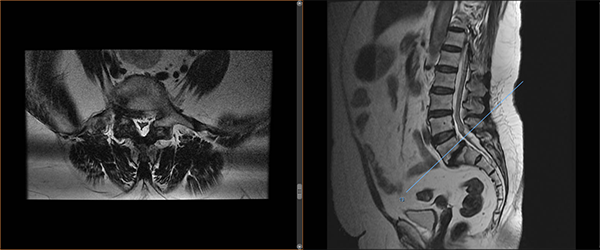

術(shù)前影像

根據(jù)覃阿姨門診腰椎磁共振顯示:腰5椎體I度滑脫伴雙側(cè)椎弓峽部裂,腰5骶1椎間盤突出合并椎管狹窄,我院脊柱外科主任胡朝暉博士及其團(tuán)隊(duì)討論研究后認(rèn)為,患者身型重度肥胖,140cm的身高體重高達(dá)72公斤,BMI指數(shù)達(dá)36.7,屬于超重范圍,開刀手術(shù)難度將升級,存在易出血多、感染幾率升高、術(shù)口相對難愈合等風(fēng)險(xiǎn),但內(nèi)鏡下腰椎融合手術(shù)較傳統(tǒng)開放手術(shù)相比,僅需要5個(gè)1.5cm的皮膚切口,具有創(chuàng)傷更小、出血更少、切口感染概率低、術(shù)后恢復(fù)快、病人術(shù)后疼痛輕等優(yōu)點(diǎn),因此內(nèi)鏡下腰椎融合手術(shù)更適合覃阿姨。